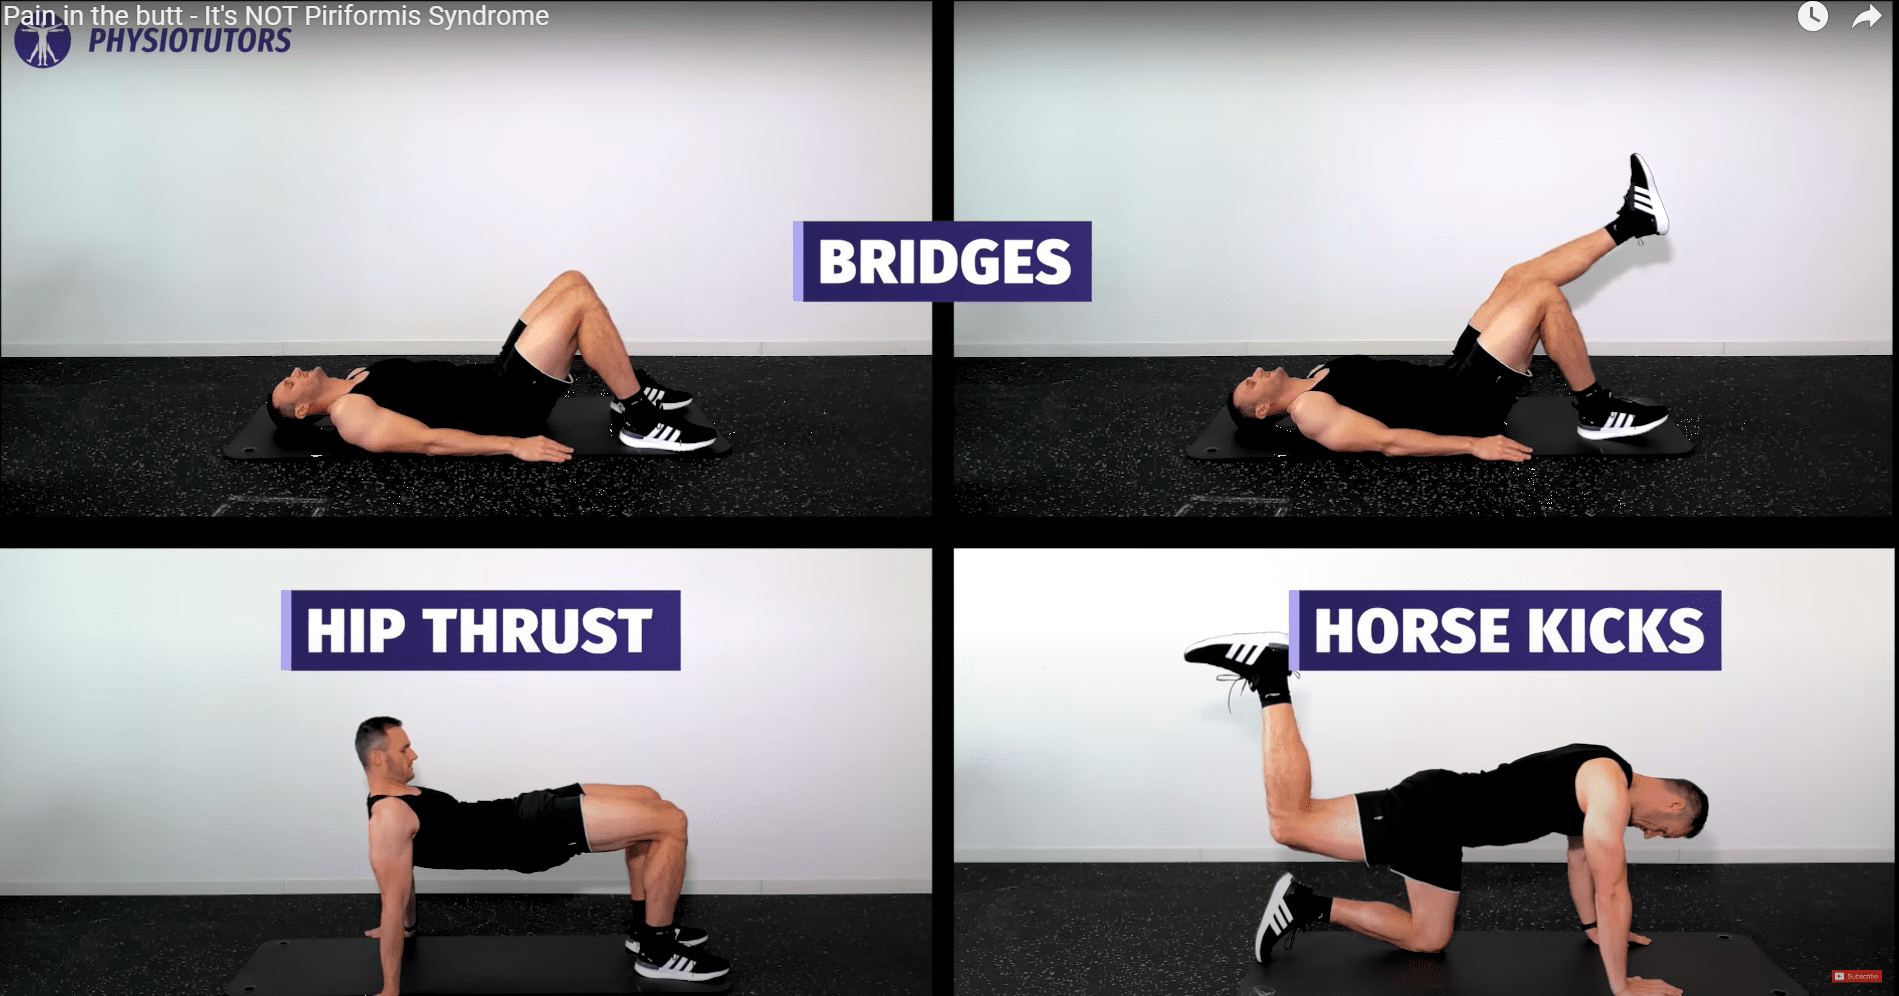

下面是一个循序渐进的锻炼计划示例,从简单的锻炼到更高级的锻炼:

- 蛤蜊壳 🡪 添加阻力带 🡪 侧平举蛤蜊壳

- 坐姿🡪🡪四足🡪🡪站姿带阻力带的消防栓

- 臀桥 🡪 单腿

- 马踢

如果这些练习可以忍受,就可以进行更重、更全面的练习,例如

- 臀部推举